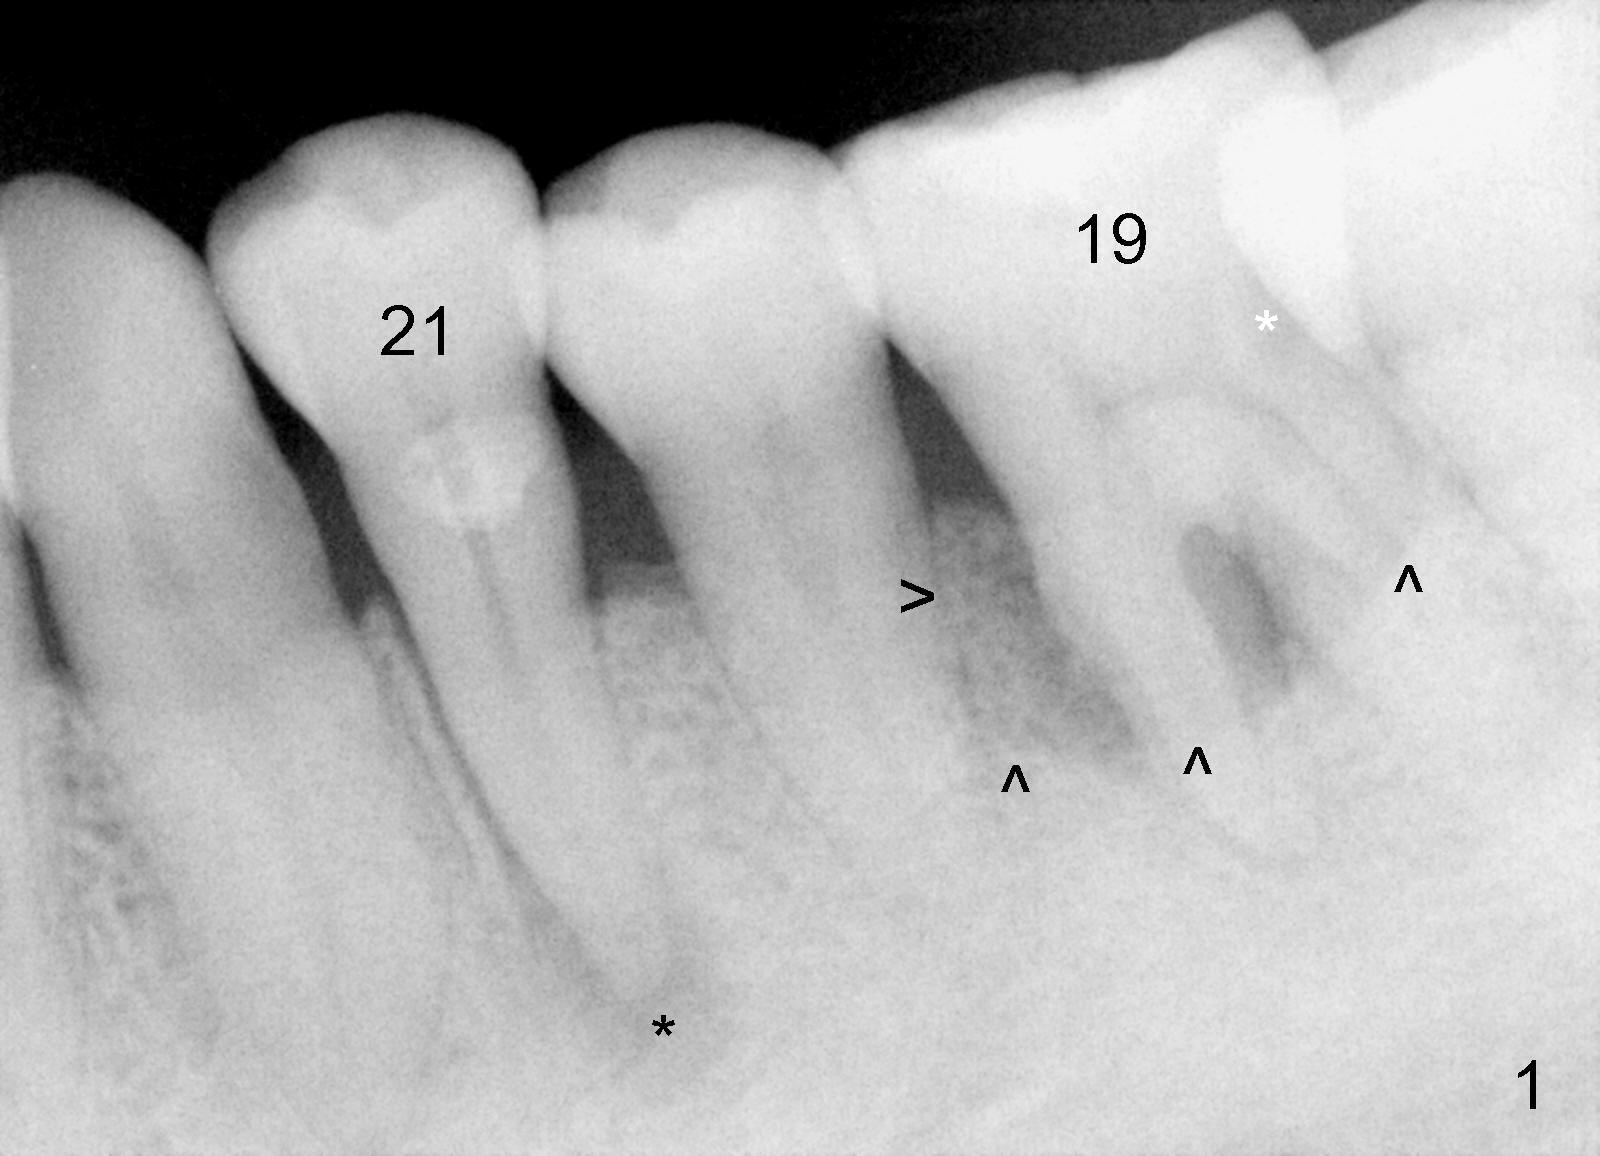

Considering severe bone resorption, a 6.9x10 mm bone-level (Fig.4) or 7x14 mm gingiva-level (Fig.5) implant does not seem to be long enough to achieve primary stability. Probably a 7x17 mm gingiva-level implant is more appropriate, but it carries more risk of nerve injury. Be careful. Take several intraop PAs for depth confirmation. Try shorter osteotomy and implant first and use longer one if necessary.